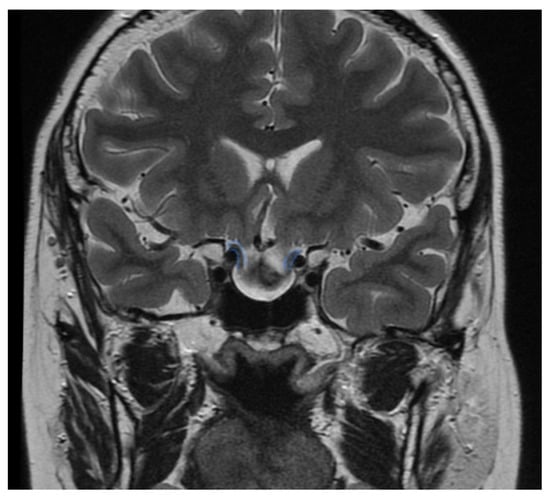

3.4. Radiological Examinations

3.5. Endonasal Endoscopic Procedures and Perioperative Complications